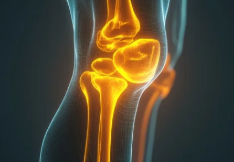

4. 오금 통증 진단 방법

✔ X-ray 검사 – 뼈 & 관절 상태 확인(관절염, 연골 손상 진단 가능)

✔ 초음파 검사 – 베이커 낭종 여부 확인

✔ MRI 검사 – 인대 손상, 반월상연골판 손상 확인

✔ 혈액 검사 – 혈전 여부 확인(심부정맥 혈전증 감별)

📌 즉, 오금 통증 원인을 정확히 파악하기 위해 X-ray, MRI, 초음파, 혈액 검사가 필요할 수 있다.